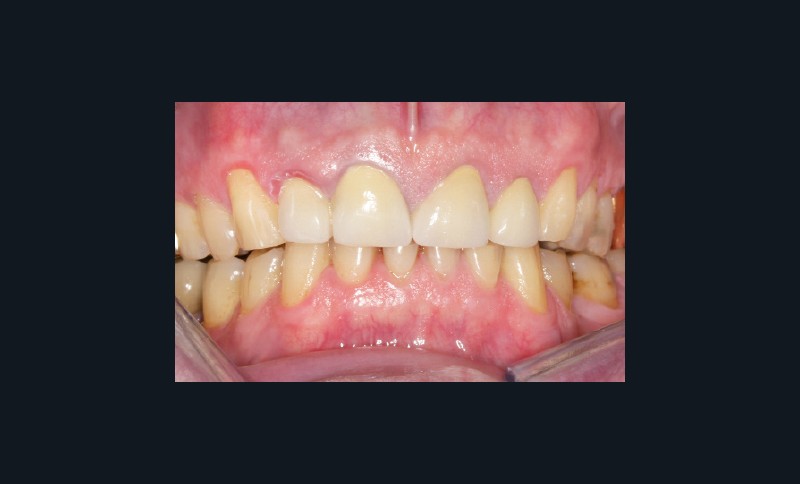

Bruxisme : net avec attrition antérieure marquée en particulier en regard des coiffes céramiques.

Occlusion : décentrage gauche, création d’une légère béance antérieure probable conséquence

de l’atteinte de l’ATM gauche.